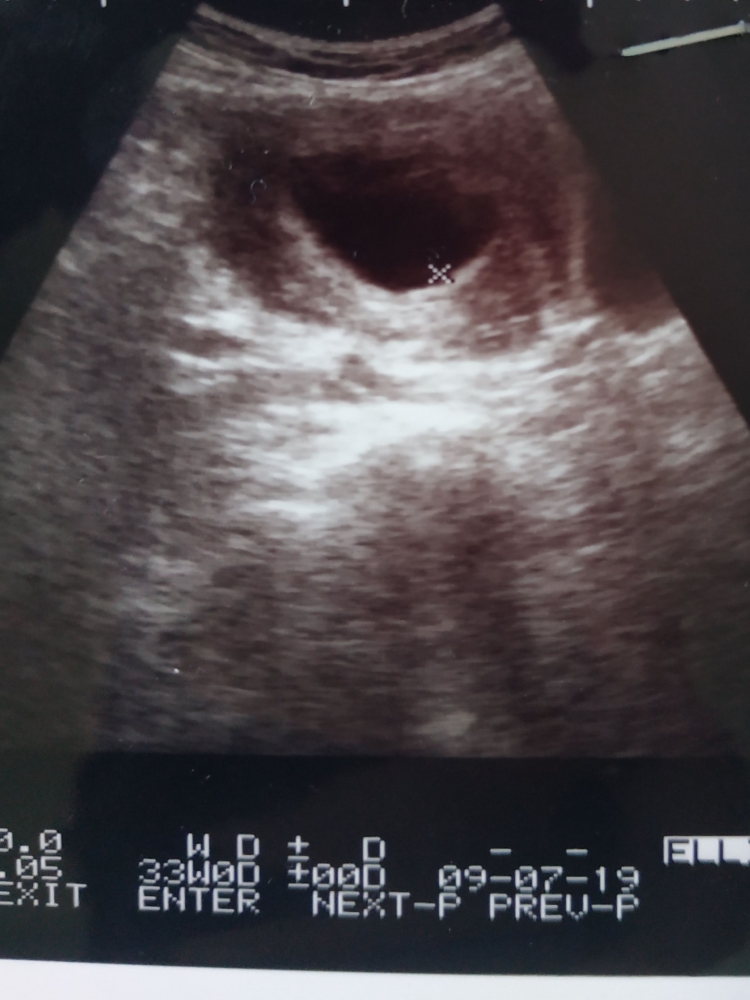

Usg 5 Minggu Belum Terlihat. Tunggu saja dengan bertambahnya usia dan besarnya maka akan semakin terlihat. Janin biasanya baru terlihat pada USG transvaginal antara 3 hingga 5 minggu kehamilan atau pada saat hCG telah mencapai 1500 hingga 2000. Bila kurang dari itu tentu Anda tidakakan melihat apapun di dalam perut Anda. Sebetulnya kalau mau USG saat usia janin 5 minggu apakah sudah bisa terlihat.

Ternyata Alhamdulilah hasil USG nya kantung janin sudah terlihat tapi janinnya belum usia kehamilan diperkirakan 6 minggu.

Janin Belum Terlihat Saat Usg Jangan Khawatir Moms Susistory. Karlina Lestari - Selamat pagi MPBiasanya janin akan terlihat di USG pada usia kehamilan 5-10 minggu namun tiap orang berbeda-beda faktor yang menyebabkan perbedaan tersebut ad. Dr Musa ini orangnya baik ramah dan lucu banget beliau bilang saya datang 2 minggu lagi untuk dicek apakah sudah ada janinnya. Selain itu bila tidak ada konfirmasi kadar hCG atau bukti pasti tentang tanggal kehamilan kehamilan Anda tersebut mungkin masih dalam tahap yang sangat awal. Melakukan USG di trimester pertama bisa dilakukan setelah kehamilan berusia 4-5 minggu.

Itu pun terlihat sangat kecil dan biasanya janin membentuk huruf C yang merupakan kepala kaki dan tali pusat dengan panjang 0635 centimeter. Parents melansir kira-kira 6 minggu setelah periode haid terakhir atau pada kehamilan 6 minggu janin dapat terlihat pada USG. Karlina Lestari - Selamat pagi MPBiasanya janin akan terlihat di USG pada usia kehamilan 5-10 minggu namun tiap orang berbeda-beda faktor yang menyebabkan perbedaan tersebut ad. Dr Musa ini orangnya baik ramah dan lucu banget beliau bilang saya datang 2 minggu lagi untuk dicek apakah sudah ada janinnya. Masih ada kemungkinan kantung janin segera tampak di minggu berikutnya.

Sama bun saya juga gtu 2 hari yg lewat saya usg menurut HPHT usia nya udah 10 minggu tpi janin nya juga belum terlihat dan dr. Tetapi janin masih juga belum terlihat di alat USG. Beberapa kasus bahkan menunjukkan janin baru akan terlihat pada saat kehamilan memasuki usia 8-12 minggu. Pada umumnya janin akan terdeteksi USG saat usia kandungan 6-8 minggu ke atas dan jika baru terlihgat kantung saja dokter kandungan akan menyarankan pemeriksaan ulang saat usia 8 minggu ke atas. Seperti diketahui USG dapat.